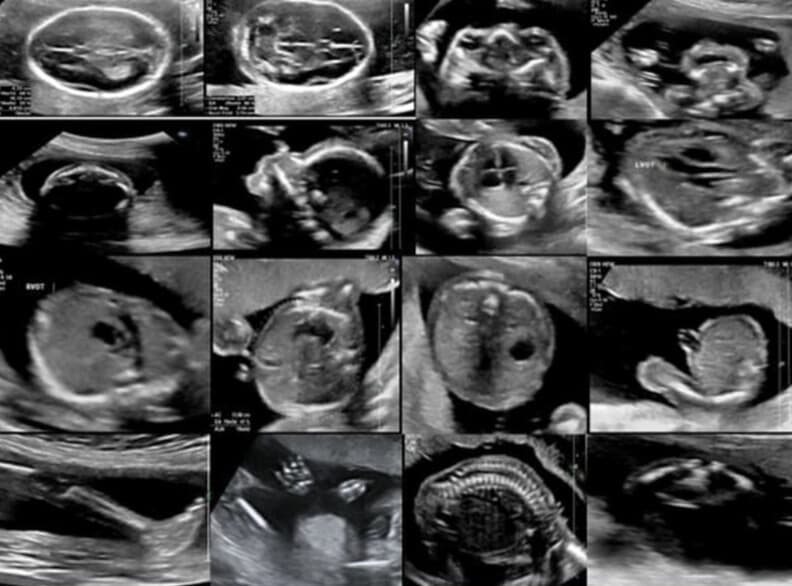

Comprehensive fetal assessment at 18-22 weeks of pregnancy

An anomaly scan, also known as a detailed fetal ultrasound or level 2 ultrasound, is a comprehensive examination of your baby's development at 18-22 weeks of pregnancy. This scan provides detailed information about your baby's growth, development, and any potential structural abnormalities.

The optimal time for an anomaly scan is between 18-22 weeks of pregnancy. During this period, the baby's structures are well-developed and visible, allowing for a thorough examination of all organs and systems. During the 20-week scan, heart abnormalities like holes larger than 5mm or any malformation in the arteries can be clearly seen.